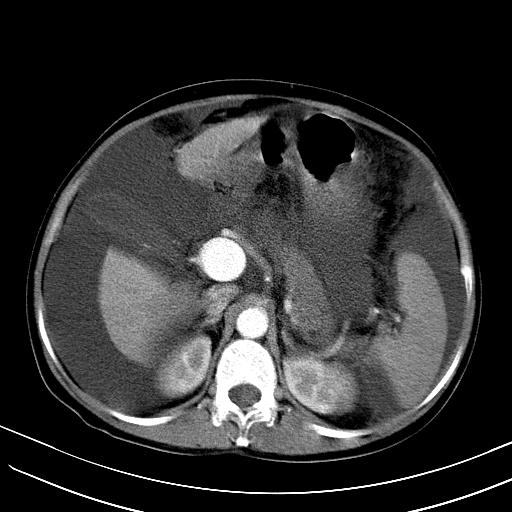

标题: CT23697:肝癌并肝动静脉漏? [打印本页]

标题: CT23697:肝癌并肝动静脉漏?

1)肝右叶肝癌并肝动静脉漏。2)肝硬化,腹水。3)胆囊炎。

肝右叶肝癌并动静脉漏,肝硬化,腹水。

1)肝右叶肝癌并肝动静脉漏 门v右支瘤栓伴海绵样变。2)肝硬化,脾大 腹水。3)胆囊炎。门v高压.

右叶肝癌并肝动静脉漏(动脉期肝动脉及门静脉内均可见造影剂),肝硬化,腹水。(胆囊壁水肿)

1)肝右叶肝癌,考虑并发肝动静脉漏。扫描时间好像慢了。2)肝硬化,门脉高压、脾大、腹水。